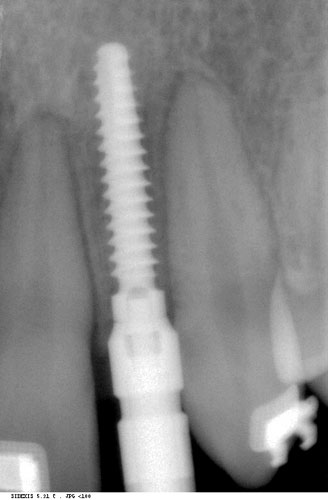

Ästhetik von Implantaten

Im Vergleich zu Kronen auf natürlichen Zähnen sind Implantatkronen meist schöner, da natürliche Zähne durch den Zahnnerv oder eine ungünstige Position die Möglichkeiten von Zahnarzt und Zahntechniker einengen. Außerdem ist der natürliche Rückzug des Zahnfleisches an Implantaten deutlich geringer als an den eigenen Zähnen - im sichtbaren Bereich ein deutlicher Vorteil.